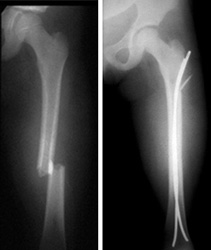

Left, Preoperative X-ray of a child with a fracture through the midshaft of the left femur. Right, Postoperative X-ray of the same child shows that the fracture was treated with internal flexible nailing to restore stability and allow early mobilization.